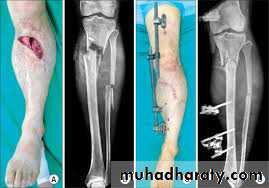

OPEN FRACTURES

The treatment of open tibial fractures is:• antibiotics

• debridement

• stabilization

• prompt soft-tissue cover

• rehabilitation.

It is important to stabilize the fracture. For Gustilo

I, II and IIIA injuries, locked intramedullary nailing ispermissible as definitive wound cover is usually possible at the time of debridement. For more severe grades of open tibial fracture, internal fixation should be performed only at the time of definitive soft tissue cover. If this is not feasible at the time of primary debridement, the fracture should be stabilized temporarily with a spanning external fixator.

Severe grades of open fractures should, when ever possible, be managed from the outset under the combined care of an orthopaedic surgeon and a plastic surgeon for soft tissue cover.